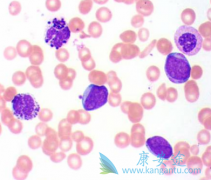

尼洛替尼 (Nilotinib)获批治疗1岁及大于1岁的儿童慢性粒细胞白血病患者是基于CAMN107A2120和CAMN107A2203两项临床试验。这些患者可以是新诊断的Ph染色体阳性且处于慢性期者,也可以是以往经过酪氨酸激酶抑制剂治疗却发生耐药或不耐受者。这两个实验中 ...

ENESTchina是一项随机、多中心试验,纳入267例新诊断(≤6个月)的c-CP成人患者,随机给予尼洛替尼( 达希纳 )300mgBID(n=134)或伊马替尼400mgQD(n=133),并根据Sokal评分和既往是否接受干扰素治疗对患者进行分层。结果显示,与伊马替尼组相比,尼 ...